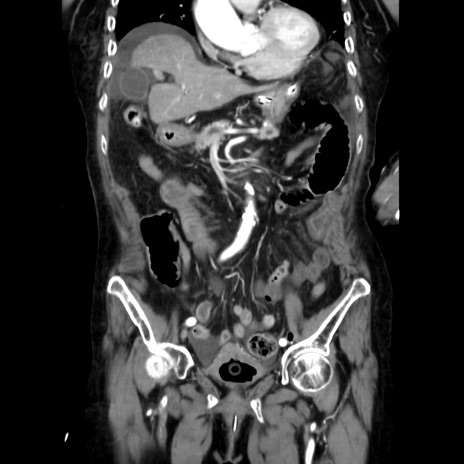

症例40(冠状断像)

【症例】90歳代女性

【主訴】腹痛・嘔吐

【現病歴】 食欲低下、嘔吐があり昨日他院受診。肺炎と診断され入院となる。入院後より腹部全体に圧痛あり。胃管留置され経過みていたが、症状持続するため、

当院転院となる。

【身体所見】腹部:中央に激痛あり、圧痛あり、反跳痛不明

【データ】WBC 17100、CRP 18.82

冠状断像